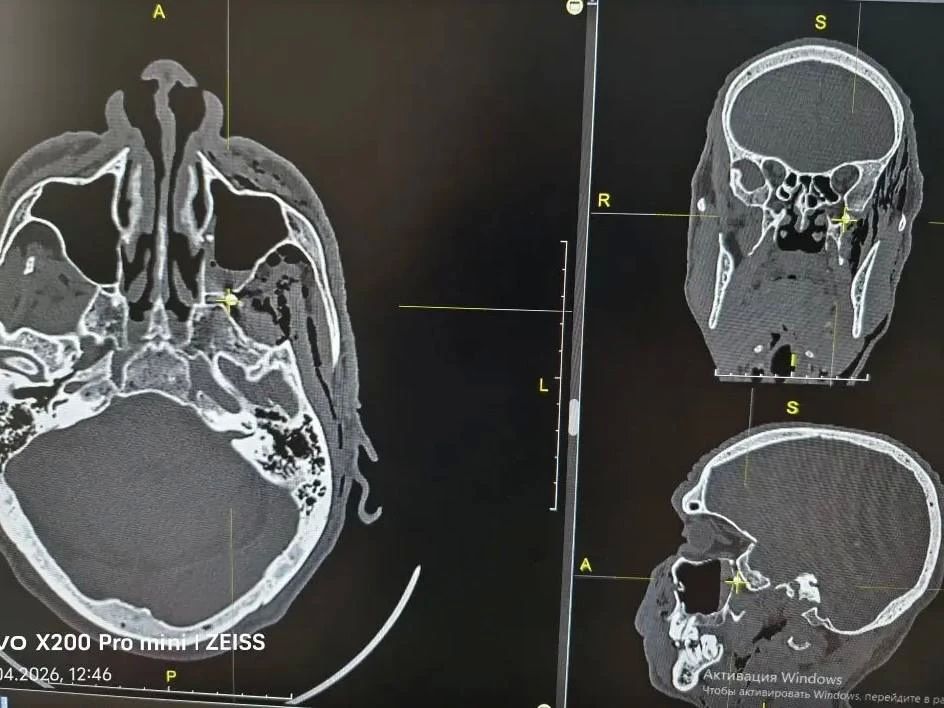

В него выстрелил соседПуля прошла через переднюю и заднюю стенки верхнечелюстной пазухи и остановилась в крыло-небной ямке — анатомическом центре, где проходят нервы и сосуды, рассказали в городской больнице Орска. Эта область соединяется с глазницей...